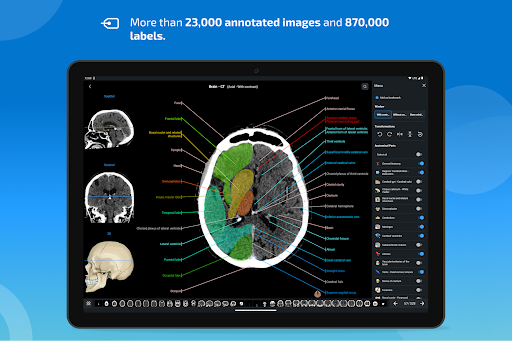

e-Anatomy memiliki lebih dari 26.000 gambar yang berisi serangkaian gambar dalam tampilan aksial, koronal, dan sagital serta radiografi, angiografi, gambar diseksi, bagan anatomi, dan ilustrasi. Semua gambar medis diberi label dengan cermat, lebih dari 967.000 label tersedia dalam 12 bahasa termasuk Terminologia Anatomica Latin.

- Ketuk label untuk menampilkan struktur anatomi

- Pilih label anatomi berdasarkan kategori